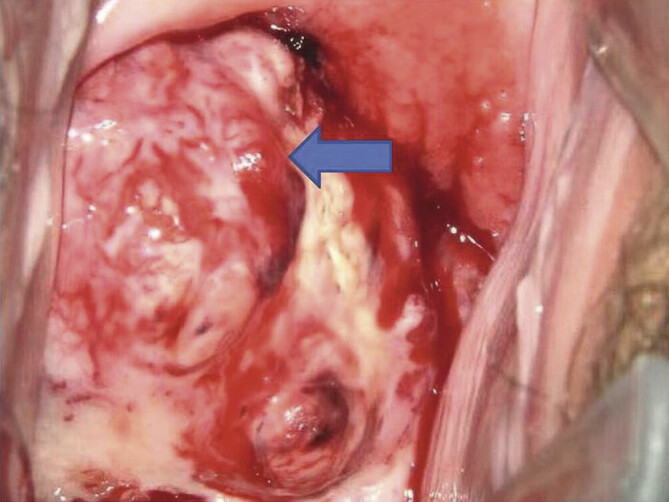

Abstract Image